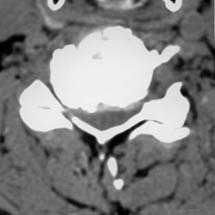

Enlargement of the spinal canal in the cervical spine

Narrowing of the spinal canal is caused by disc wear, bone attachments (so-called osteophytes), changes in the vertebral joints (spondylarthritis) and due to thickening (hypertrophy) of the so-called yellow bands (ligaments flava). The narrowing of the spinal canal can be of varying degrees and can be implied for different lengths (i.e. a different number of levels). The result of spinal canal narrowing is a pressure of the structures that are located in the spinal canal (nerve, spinal cord)which can therefore no longer exercise their function. This leads to numbness, paralysis, unsteadiness and ultimately to bladder dysfunction. These disorders can be regressed at the beginning (i.e. are reversible). When the pressure was too strong and too long, however, there is a death of nerve cells and then despite an operation, no more improvement can be achieved.

The aim of an operation is to decompress (i.e. discharge of the depressed nerves and spinal cord). This can be done in various ways, such as by surgery from the rear, i.e. the neck, with removal of compressive structures and an additional stabilization, so a deformity (e.g. kyphosis) does not occur. Due to the discharge, conditions are being created for function to be able to improve.